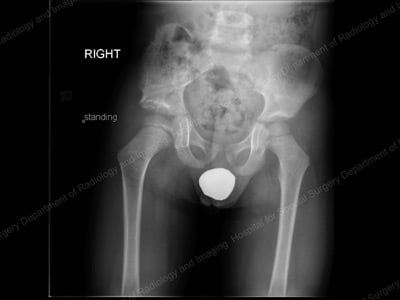

Anterior-to-posterior (front-to-back) X-ray showing residual

acetabular dysplasia on the right hip (shown at left).

Immediate postoperative X-ray after Dega pelvic osteotomy.

X-ray: Pelvis and hip 18 months after Dega pelvic osteotomy.